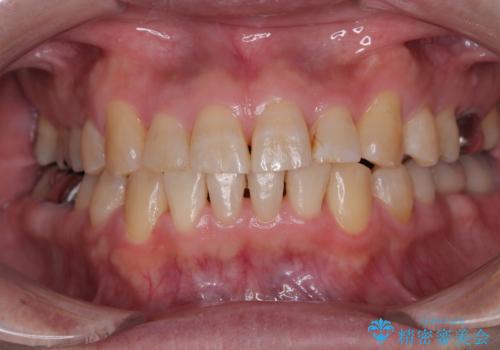

- 隙間をセラミックで閉じたら不格好で歯肉から出血 矯正治療と歯周外科で綺麗な前歯に